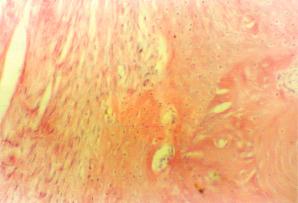

從形態學上可分為破壞性和增殖性兩類,暴髮型及局限型兩種大體可見局部頭皮腫脹,有波動感的頭皮下膿腫和慢性竇道在其鄰近的部位有單發或多發的形狀及大小不等的顱骨缺損,其中,有游離的碎骨片也可見顱骨呈凹凸不平的蟲蛀樣破壞改變病變顱骨呈灰黃色,無光澤,質松軟內含膿液。竇道內及硬腦膜外有大量黃色黏稠膿液,肉芽組織增生及硬腦膜增厚變脆。顯微鏡下可見病變組織中有大量膿球滲出及白細胞浸潤纖維結締組織及血管增生,骨小梁破壞正常結構模糊不清。

化膿性顱骨骨髓炎病理圖鑑別診斷:

化膿性顱骨骨髓炎病理圖其它輔助檢查: